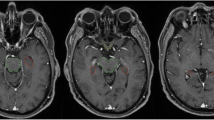

T1 contrast medium enhanced magnetic resonance imaging (MRI) scans of 865 patients with brain metastases (4,280 metastases) were reviewed. HT-P area was individually contoured with a margin of 5 mm in order to evaluate the prevalence of brain metastases in this region.

Pre-treatment gadolinium-enhanced T1-weighted magnetic resonance image (MRI) datasets of 865 patients with brain metastases from the years 2014–2018 were reviewed at the University of Luebeck, Germany. The HT-P area was contoured on axial planes for each patient as described previously by others [20, 21]. In short, minimal requirements for sufficient contouring and delineation were as following: CT images (axial planes) were fused to images obtained via T1-weighted MRI images (gadolinium contrast enhanced) acquired on 1.5 T resonance scans with a slice thickness of 1.5 mm. The hypothalamus and pituitary gland (including the pituitary stalk) were contoured on T1-weighted axial MRI sequences and a margin of 5 mm was added (see Fig. 1) [20, 21].

A total number of 4,280 brain metastases in 865 patients were identified with a mean of 5 metastases per patient. Individual maximum size of metastases ranged from 0.2 to 11 cm (median: 1.8 cm). Patients mean age was 64 years (range: 29–90 years) and the primary tumor entity was non-small cell lung cancer (NSCLC) in 46% of the patients. Patient and disease characteristics are summarized in Table 1. Involvement of the hypothalamus region (hypothalamus + 5 mm) was found in 26 patients translating to HT involvement of ~ 3% of patients and ~ 1% of all metastases. Involvement of the pituitary region (pituitary gland + 5 mm) was observed in 9 patients, i.e. 1% of all patients and < 1% of all metastases, respectively. Binary logistical regression models revealed a high number of metastases, i.e. > 10 vs. < 3 metastases as the only factor significantly associated with hypothalamic involvement (p = 0.0002; Table 2). In contrast, examined factors were not related to the involvement of the pituitary gland region (Table 3).